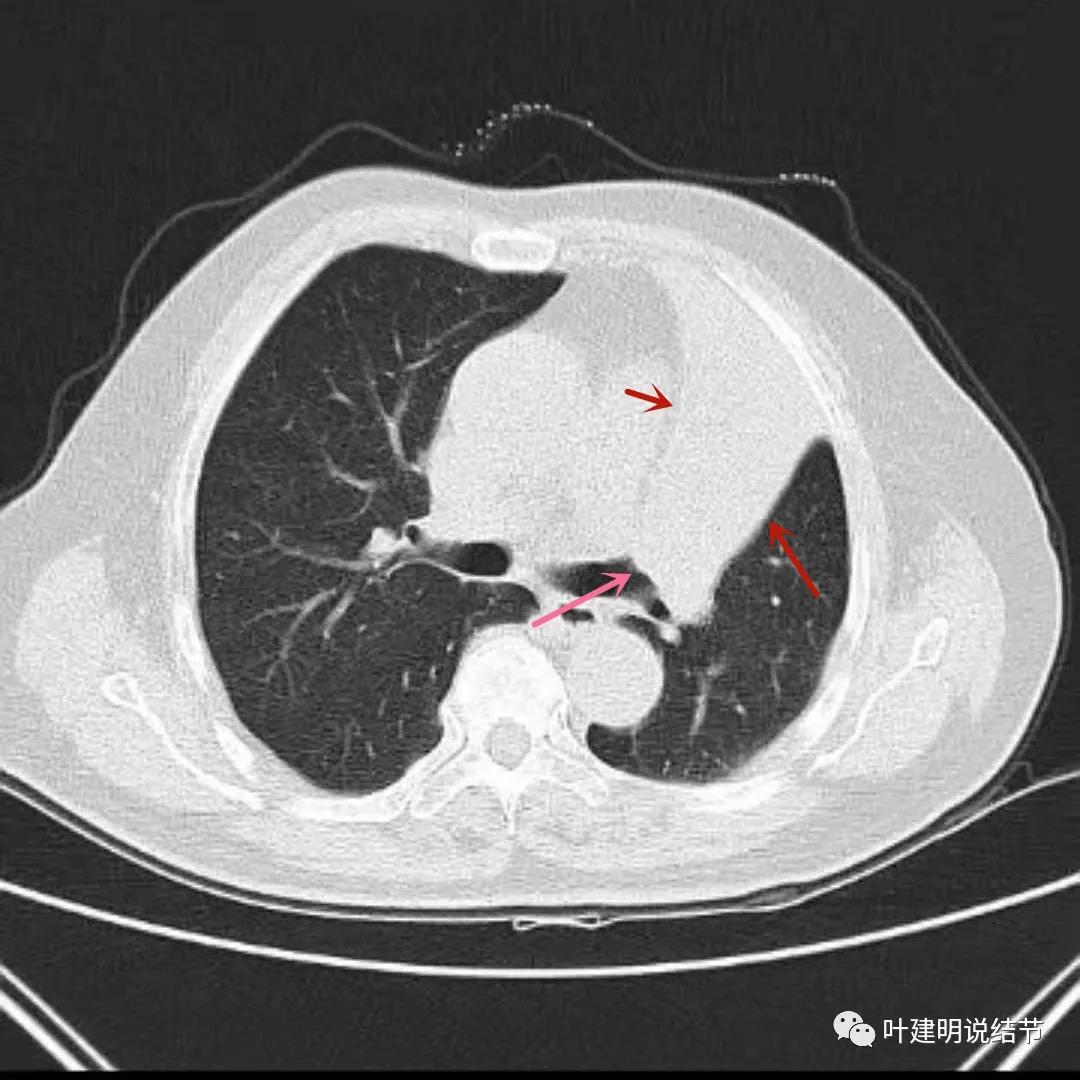

上图见左上叶实性密度影,粉色箭头示病灶影响左上叶支气管开口,且不平整

上图与左上叶不张与肿瘤以及蓝色箭头所示的左下叶支气管腔是通畅的